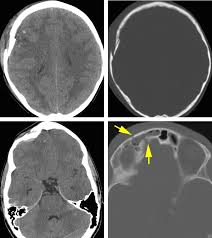

18+ Posterior Cranial Fossa Fracture Signs Pictures. The posterior cranial fossa is the most posterior aspect of the skull base housing the brainstem and cerebellum. Anteriorly it extends to the apex of the petrous temporal.

The posterior fossa contains the cerebellum, brainstem and 4th ventricle and is separated from the supratentorial compartment by the tentorium. The body of the sphenoid makes up the. It houses the cerebellum, medulla and pons.

The posterior cranial fossa is located behind the superior border of the petrous temporal bone and the dorsum sellae of the sphenoid and is the deepest of all cranial fossae. The posterior cranial fossa is the rearmost hollow or depressed area in the base of the cranium. Anteriorly it extends to the apex of the petrous temporal. The posterior cranial fossa is the most posterior and deep of the three cranial fossae.